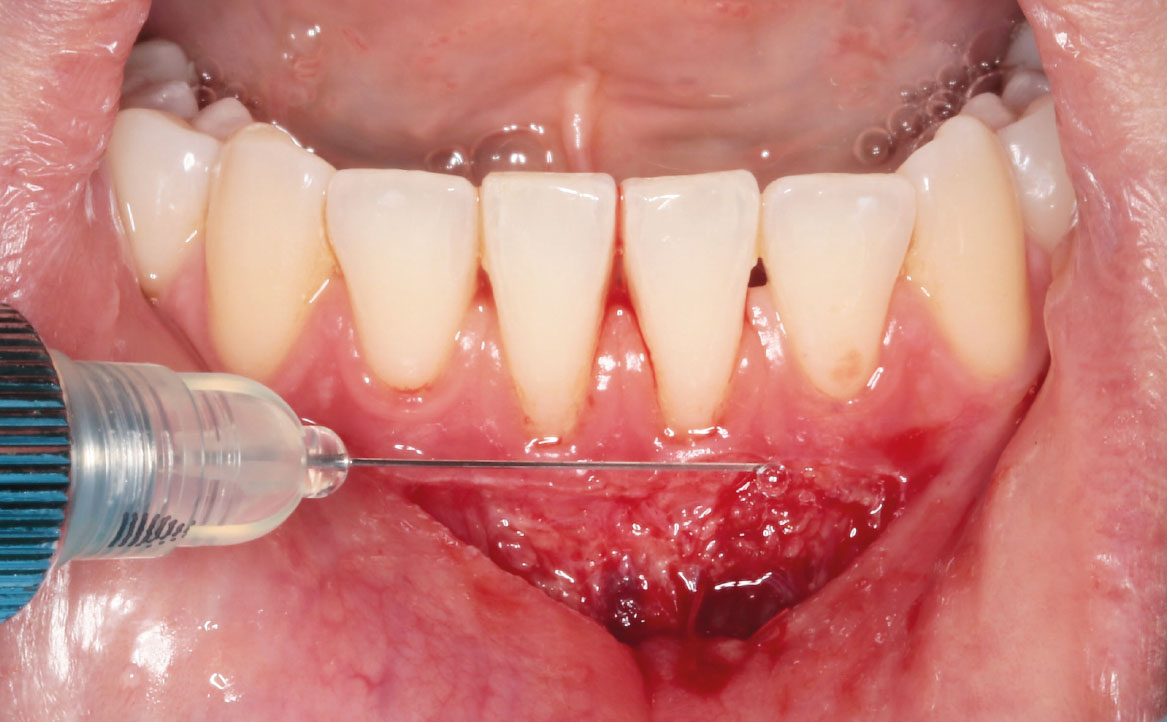

Successivamente, i margini epiteliali e il tessuto sottomucoso sono stati fissati con punti di sutura singoli usando fili riassorbibili 5/0 Vicryl (fig. 6). Sul fondo del difetto chirurgico è stato applicato un gel di acido ialuronico reticolato, xHyA (composizione: 1,6% acido ialuronico reticolato, 0,2% acido ialuronico nativo) (fig. 7). L’acido ialuronico (o ialuronano, HA) è un glicosamminoglicano formato da un’unità disaccaridica (acido glucuronico e N-acetilglucosammina) che si ripete fino a 50.000 volte. Questa molecola è normalmente presente nel nostro organismo dal momento che rappresenta uno dei principali componenti della matrice extracellulare (5). L’HA è una sostanza igroscopica e viscoelastica (6), che svolge un’azione batteriostatica (7), antinfiammatoria (8,9) e antiedematosa (10). Inoltre, lo ialuronano sembrerebbe rivestire un importante ruolo nella rigenerazione tissutale, prendendo parte e accelerando le fasi del processo di guarigione delle ferite (11,12).